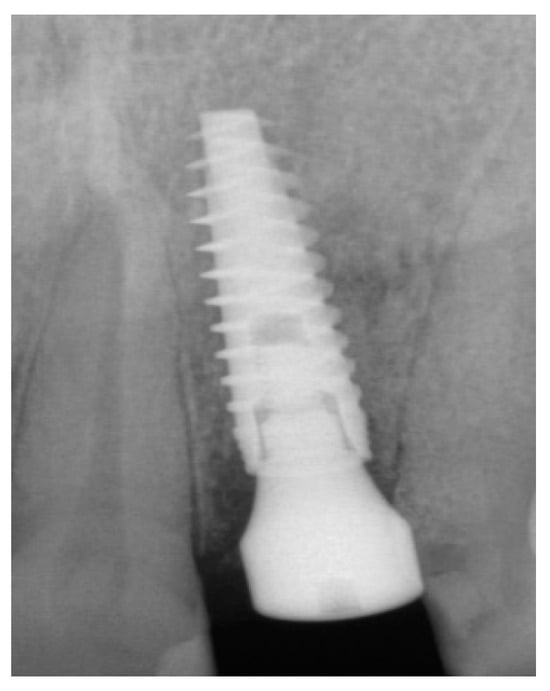

The patient accepted the proposed treatment plan. The preoperative surgical protocol described in patient 1 was followed. An L-shaped aesthetic flap design was chosen to treat this case. The flap started with an incision extending from the distal line angle of the central incisor to the mesial line angle of the canine. A vertical incision was carried out past the mucogingival junction, followed by the elevation of a full-thickness flap. The remaining tooth root was extracted, maintaining the existing facial bone (Figure 9).

Figure 9.

Clinical view of implant replacing.

The surgical protocol was followed as described for the previous patient. Likewise, an implant was placed, followed by the placement of bone graft material over the defect and covered with a resorbable membrane. Six months later, the implant was fully intergraded (Figure 10), and the soft tissue appeared to be within normal limits (Figure 11). The implant was restored with a ceramic zirconia crown. Figure 12 presents the patient three years after treatment.

Figure 10.

Radiograph of the lateral incisor.